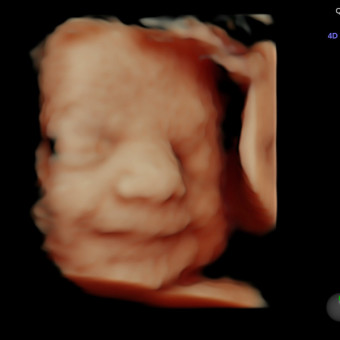

Jasmin & Justin’s Baby Registry

Jasmin & Justin Divitto

May 31, 2026

The grand finale, baby #3 is on her way!